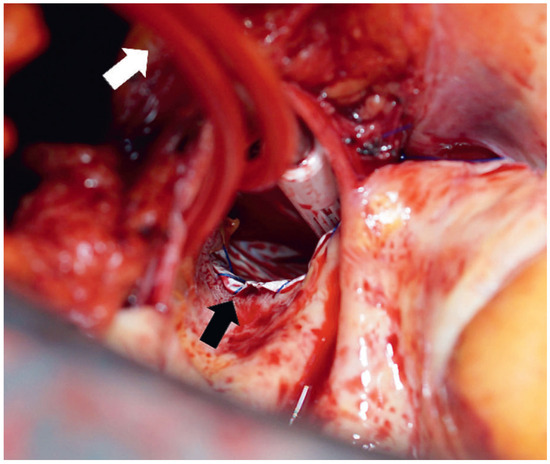

Veno-arterial extracorporeal membrane oxygenation (ECMO) is utilised as a short-term mechanical circulatory assist device for treatment of refractory acute cardiogenic shock. After a period of support, called “bridge to decision”, the options for ens...